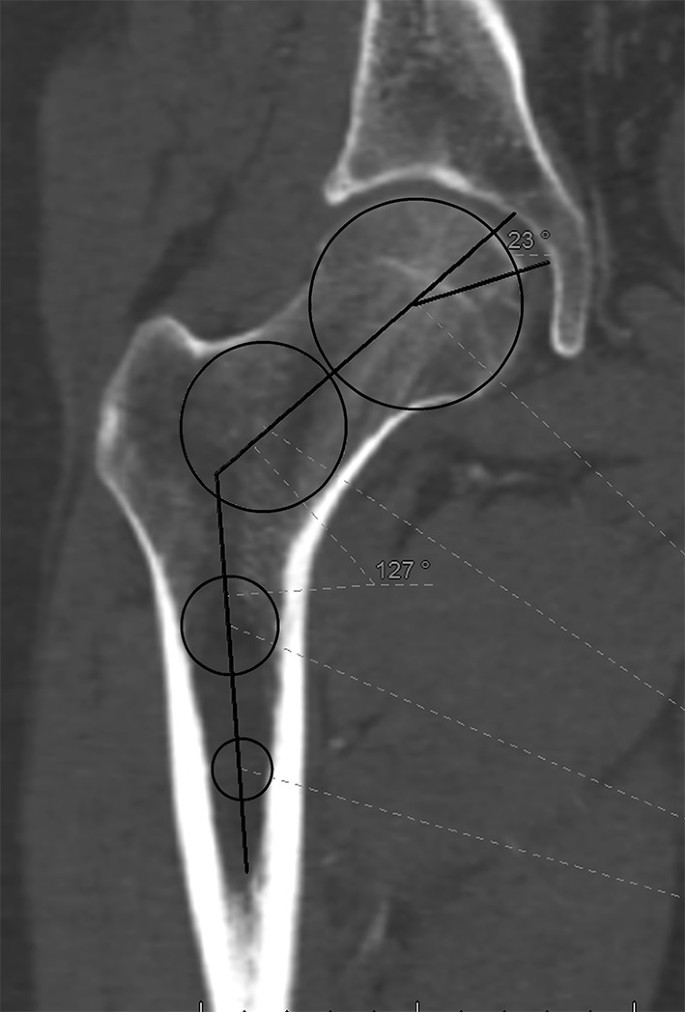

The semi-coronal plane, that corresponded to the exact anteroposterior view of the femur, was used to assess the neck–shaft angle, the size of the femoral head, the size of the fovea, and the position of the fovea in relation with the neck axis (fovea angle), as shown in Fig. 1. The femoral neck longitudinal axis was drawn in both planes, using the slices, where the femoral head was at its greatest diameter. The midpoint between the cortices in the femoral neck and the middle of the femoral head served as reference points for determining the axis of the neck in the semi-coronal plane. Centroids were used to exactly determine the midpoints of the femoral head and between cortices (Fig. 1). The axis of the femur was determined as a line passing through two points: one midway between the femur cortices approximately 2–3 cm distally to the lesser trochanter (as far distally the range of the scan and the quality of the image allowed) and one at the upper border of the lesser trochanter. The angle was measured at the intersection between those two lines. A CT scan of the whole femur was available in 13 cases, and the accuracy of this measurement was checked with relation to the shaft axis of a whole femur semi-coronal scan. It showed that the measurement of the femoral shaft axis on the shorter scans was accurate within a mean of 2.100 (range 0–3) deviation from the whole bone scan, what was considered a good approximation between both methods.

Fig. 1

figure 1

Semi-coronal view of the femur shows the neck–shaft angle and the fovea angle

The position of the fovea in the semi-coronal plane was assessed as the angle between the femoral neck axis and a line drawn between the center of the femoral head and the upper border of the fovea.